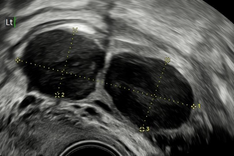

b) diagnostikou a léčbou endometriózy, neplodnosti a chronických pánevních bolestí

c) diagnostikou, konzervativní i radikální léčbou děložních myomů

d) poruchami hojení jizev na děloze po císařském řezu (tzv. niche)